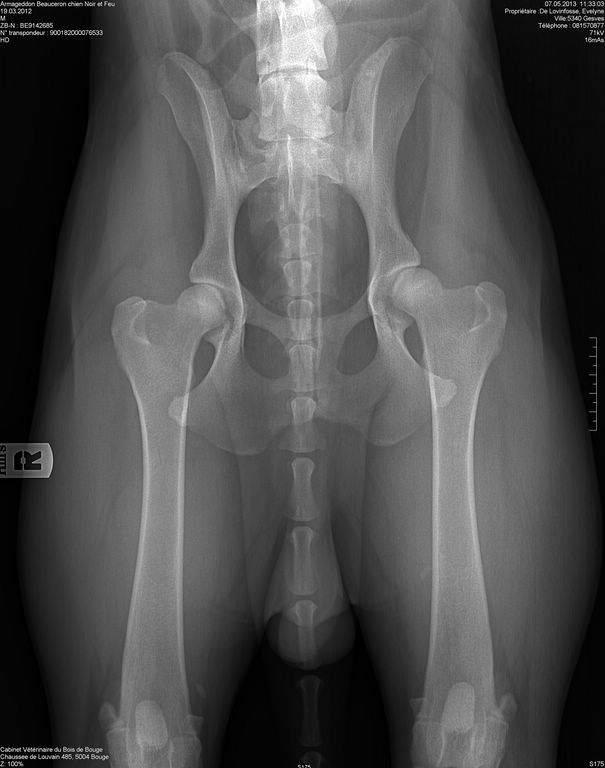

Ch.Armageddon du Gardiens du Chaos

Né le 19/03/2012 Pedigree MET 365/12 - LOSH 9142685

Cotation 4 - Recommandé HD B1 ED 0/0 (B)

HD A (F)

"Aragon"